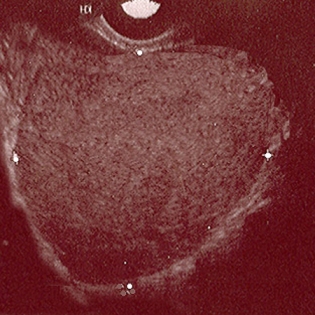

- pelvic ultrasound:

may show ovarian endometrioma (homogenous low-level echoes) or evidence of deep pelvic endometriosis such as uterosacral ligament involvement (hypoechoic linear thickening)

enlarged uterus with heterogeneous texture, no well-defined masses